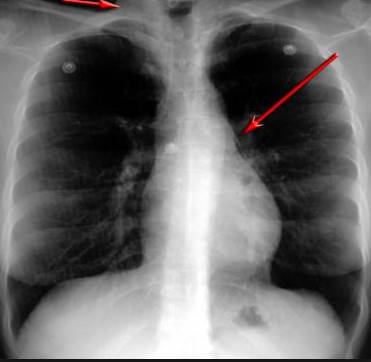

并且,因為呼吸系統(tǒng)結(jié)構(gòu)復(fù)雜,在體檢時醫(yī)生很難通過一種檢測手段,判定早期患者的病情。

使用這臺掃描儀,將直接把器官變成3D圖形!細(xì)微的毛細(xì)血管,幾毫米大的肺泡和支氣管,都將能看的一清二楚!

你的每一個氣泡,每一段支氣管,哪兒有病變都清清楚楚的將展示在醫(yī)生面前!

也就是說在一切都還沒開始惡化前,把這些有問題的器官組織都暴露的一清二楚:

這臺儀器不僅僅是一臺能拯救幾百萬條生命的高清掃描儀,它更是一場開天辟地的技術(shù)革新!因為它不僅能幫醫(yī)生看到肺病的結(jié)構(gòu)圖,

還能看到器官是如何運動的!

空氣是如何進入到肺部,氧氣是如何到血液,任何微小的變化都將曝露在醫(yī)生面前!更清晰的圖像,更細(xì)節(jié)的變化!

不同于CT掃描,需要從同一角度,拍下無數(shù)張器官二維圖,從而搭建3D器官結(jié)構(gòu)圖那般費時費力。

4D掃描儀將直接從不同角度,同時對人體器官進行掃描,然后通過計算機算法進行快速成像。CT需要花幾小時才能完成的工作,

4D掃描將在幾秒內(nèi)完成!

當(dāng)大家還在為B超、X光、CT哪個輻射更少而爭論不休時,這臺新機器已經(jīng)比現(xiàn)有掃描儀少20%的輻射

不需要重復(fù)拍片,輻射也更少!

沒有這項新技術(shù),醫(yī)生在做體檢的時候,很難通過一種測試斷定一個人是否有呼吸系統(tǒng)疾病。

可是現(xiàn)在他們不但能看到整個肺部的3維結(jié)構(gòu)圖。還能看到空氣進入人體后的所有微小變動!